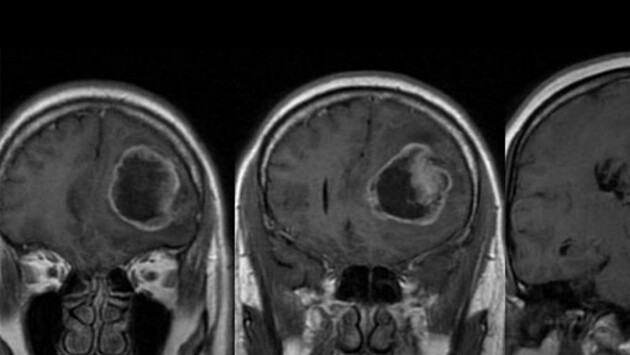

Медики создали молекулы, уничтожающие клетки рака мозга

Журнал Science опубликовал исследование ученых из Йельского университета, в котором они описали новый способ лечения рака головного мозга. Этот подход предполагает избирательное уничтожение раковых клеток с помощью прямой модификации ДНК. Для этого исследовательская группа разработала специальные молекулы, которые фрагментируются в клетках и вызывают модификации ДНК раковых клеток. В большинстве случаев, в клетках глиомы II и III степени отсутствует белок репарации ДНК O6-метилгуанин метилтрансфераза (MGMT). MGMT-дефицитные опухоли первоначально реагируют на агент метилирования ДНК темозоломид, однако потом приобретают устойчивость. Разработанные учеными молекулы преодолевают этот механизм резистентности, избирательно индуцируя гибель клеток в опухолях. Эти агенты вызывают динамическое повреждение ДНК раковых клеток. По словам ученых, это открытие поможет создать новые методы лечения глиом и других видов рака. Биологи из США показали, что прием аспирина снижает риск развития рака яичников.